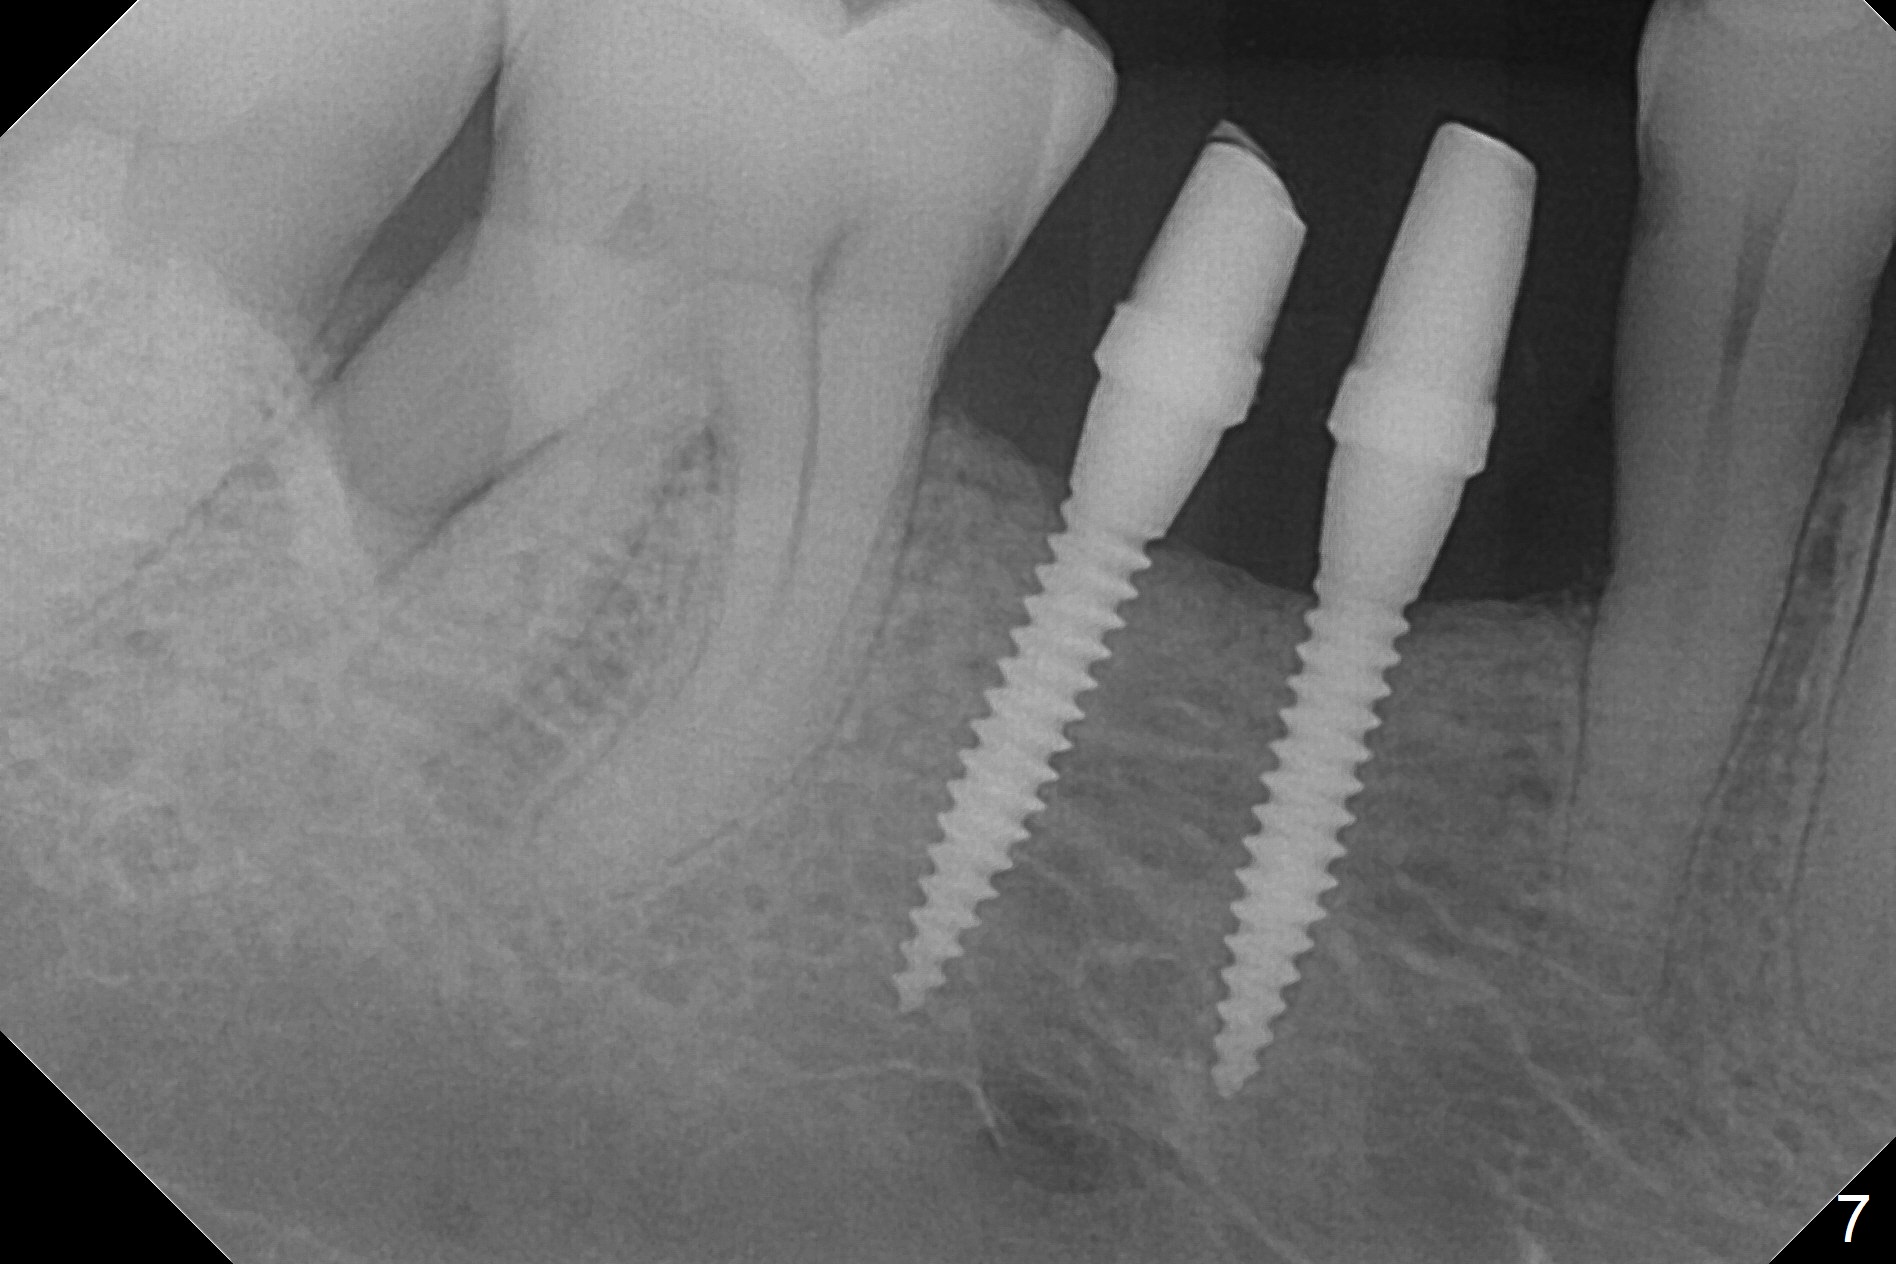

The wide mesiodistal space at #29 is most likely due to congenital missing permanent tooth (i.e., deciduous molar retention before extraction 34 years ago). The patient is now 62 years old. In fact the buccolingual width is not so narrow (Fig.1). After incision, the ridge is approximately 5 mm. Two osteotomies are established with 1.2 mm drill at 8 mm mesially and 1.5 mm one at 10 mm distally (Fig.2). The apparent approximation of the mesial osteotomy to the Mental Loop (red dashed line) is related to X-ray angulation, since there is 1-2 mm separation when two of 2x10(2) mm 1-piece implants are placed (Fig.3,4). Insertion torques of the mesial and distal implants are less than 25 and 15 Ncm, respectively. In fact bone graft is placed around the distolingual root of the tooth #30 after calculus removal (Fig.4 <). Following reduction of the abutments, periodontal dressing is applied locally. The dressing dislodged 13 days postop (Fig.5). A provisional is going to be fabricated 4 weeks postop when the wound heals (Fig.6). No bone loss is observed 4 months postop (Fig.7).